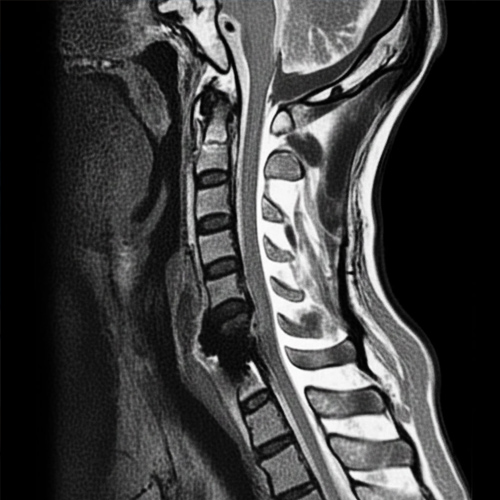

경추협착증은 경추(목 , 척추)의 척추관이 좁아져서

척추 신경이나 척수에 압박이 가해지는 상태를 말합니다.

경추(목뼈) 부의 척추관 협착증을 일컫는 말로

척추관이 좁아져 팔이나 다리로 가는 신경을 압박함으로써 증상이 나타나는 질환